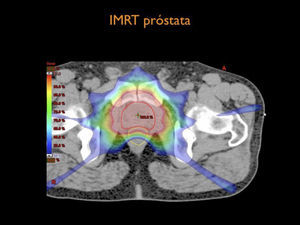

Por otra parte el desarrollo tecnológico ha sido inmenso mejorando la precisión en la distribución de la radiación con el uso de radioterapia por modulación de intensidad en su forma estática, IMRT, intensity modulated radiotherapy o modulación volumétrica de intensidad en arco, VMAT, volumetric modulated arc therapy(1) (Figura 4). Otro desarrollo fundamental ha sido la optimización en la precisión para depositar la radiación en el sitio planificado. Con el fin de optimizar la ubicación del blanco de tratamiento se han mejorado los sistemas de inmovilización y se implementó la radioterapia guiada por imágenes, IGRT (image guided radiotherapy), con campos ortogonales o mediante la obtención de TAC en la máquina de tratamiento, CBCT (one beam computed tomography) (6,7). Se implementa además el uso de marcadores fiduciales, insertos en el volumen blanco, los que facilitan la verificación de la posición del volumen (6) (Figura 5).